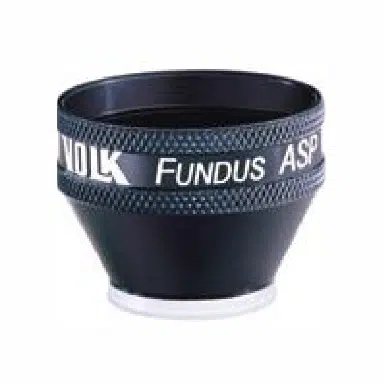

Lente Volk® Rapid SLT

Lente per gonioscopia, progettata per i trattamenti di Trabeculoplastica Laser Selettiva. Evoluzione della classica Lente SLT, infatti ha 4 specchi invece che 1 solo per una visione panoramica del trabecolato e quindi trattamenti più rapidi e precisi.

SKU: VMSLT

Category: Lenti Laser, Lenti laser speciali

Lente Volk® Rapid SLT